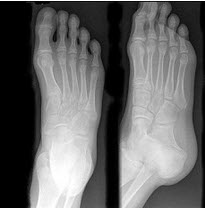

47、单项选择题

男,36岁,从高处摔下,足部受伤,结合图像,最可能的诊断是()

A.距骨骨折

B.跟骨骨折

C.骰骨骨折

D.舟状骨骨折

E.楔骨骨折